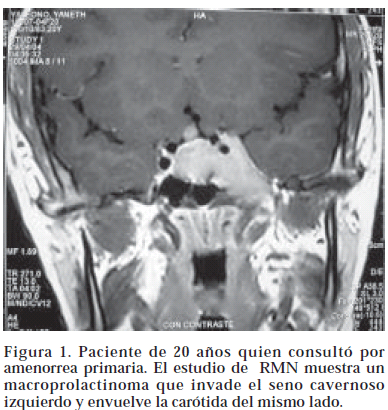

Los prolactinomas se clasifican de acuerdo a su tamaño en micro o macroadenomas Los primeros tienen menos de 10 mm de diámetro y se asocian con valores mas bajos de prolactina sérica. Los macroprolactinomas tiene más de 10 mm. y pueden a su vez comportarse en forma agresiva invadiendo los senos cavernosos, el seno esfenoidal y la cisterna supraselar5. Debido a que la cirugía transesfenoidal, normaliza los valores de prolactina solo en un 50 a 70% de los microadenomas6, esta es inefectiva en la mayoría de los macroadenomas y la recurrencia de la enfermedad es muy frecuente en el postoperatorio. El tratamiento con bromocriptina es la primera opción terapéutica en los prolactinomas. En dosis de 2,5 hasta 10 mgs por día, este medicamento normaliza los niveles de prolactina en 80 a 90% de los casos, disminuye el tamaño del tumor y mejora los campos visuales7(Fig 1 y 2). Los efectos secundarios se relacionan generalmente con la forma de administración de la droga, que debe tomarse fraccionada dos o tres veces al día y siempre con las comidas.